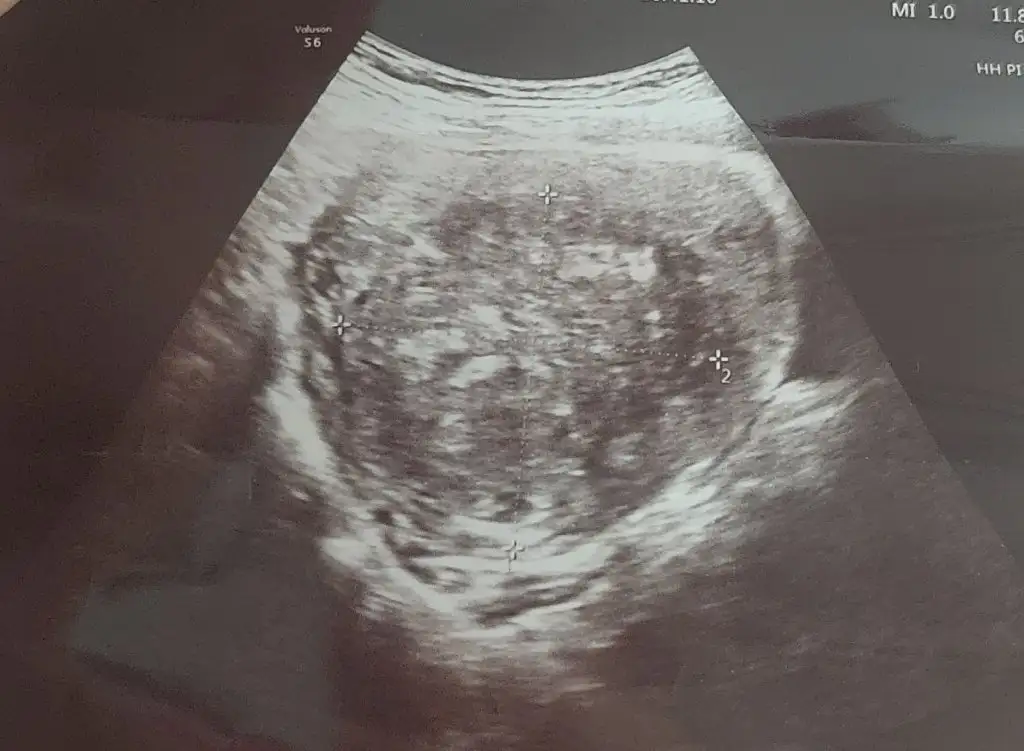

Kızlar bu arada miyom ultrason goruntum😏

Eklentiler

• IMG-20230309-WA0042.webp

IMG-20230309-WA0042.webp

32,2 KB · Görüntüleme: 87

Rahim duvarına yapışık dediğiniz içeri doğru mu büyümüştü? Bazı durumda dışa bazı durumda içe buyuyormus ya..ameliyat sonrası sanırım 4 ay gibi bi korunma suresi oluyor o da kapalı olursanız ve hersey yolunda giderse.ama rahim tam toparlanmazsa ameliyat sonrası rahimde yırtılma olabiliyormuş gerçi yorumlarda okudum bunu. Doktora gittim şöyle ki sadece ultrason çekildi mr verdi ama ben miyom var deyince doktor şok oldum devamında sersem gibi oldum gebelik düşünecektim çünkü. Sonrasinda ramazan gelince kaldi , ramazan sonrası detaylı muayene olacağım ona göre karar vereceğim. Bu arada ultrason goruntum boyle.benimde içinde degilmis doktor bu şekilde soylemisti sadece .ama içeri etki ediyordur mutlaka cunku 6 cm e yakin